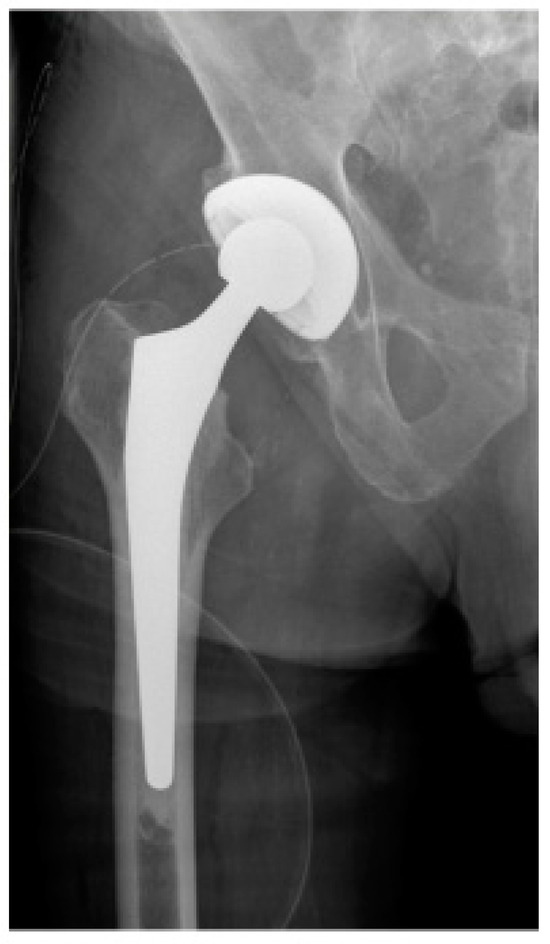

Early Postoperative Weight-Bearing Ability after Total Hip Arthroplasty versus Bipolar Hemiarthroplasty in Elderly Patients with Femoral Neck Fracture

2. Materials and Methods